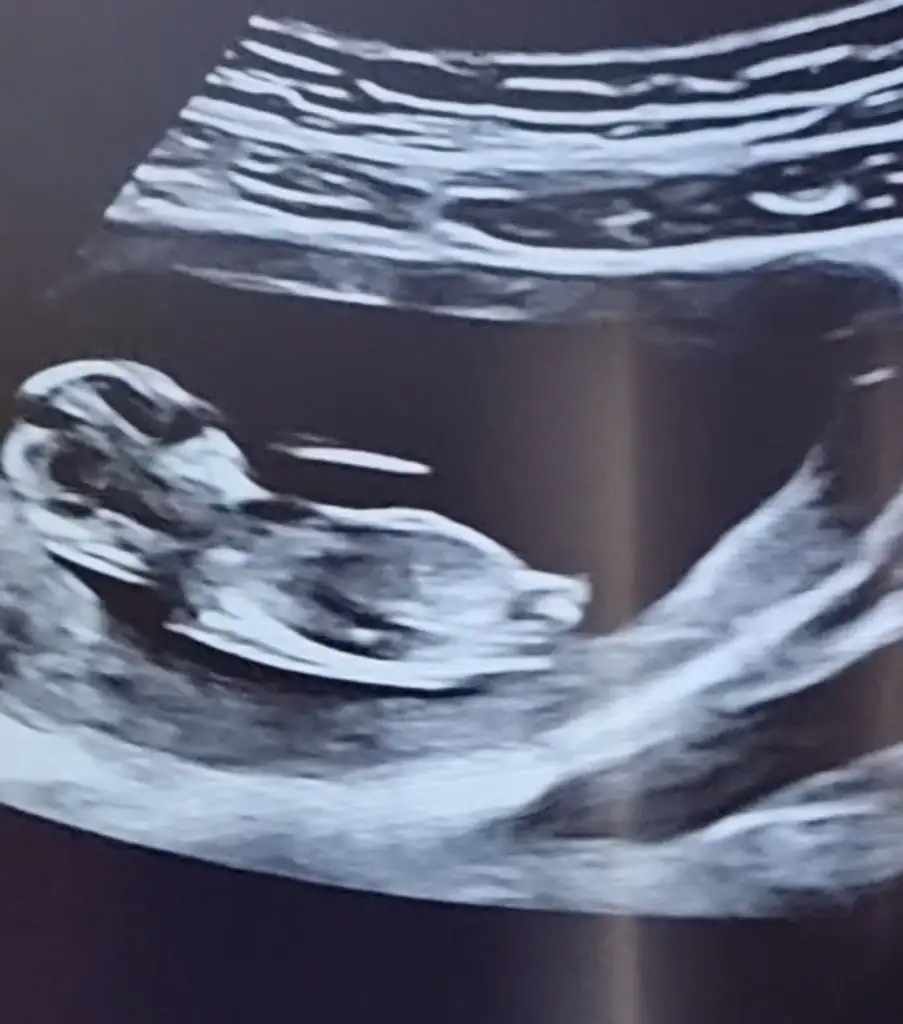

Erkek görünüyorRica etsem ben de bir tahmin alabilir miyim 11+5 ultrasonu :)

Çok teşekkürler :) Allahim hayırlı evlat versin herkese. Doktorumuz cinsiyetini söylediği zaman hemen yazicam sizeErkek görünüyor